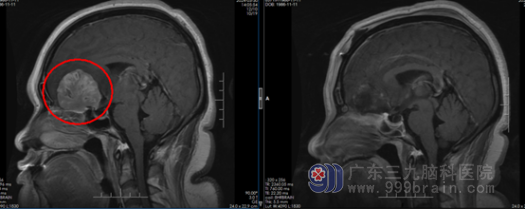

“入院时,患者的嗅觉全无,右眼视力仅剩光感,呈嗜睡状态。”根据相关影像资料,该院神经外六科副主任谭家亮发现患者的肿瘤从嗅沟向上生长,对视神经造成挤压,初步诊断是嗅沟脑膜瘤。

明确诊断后,谭家亮带领神经外六科团队为患者行前颅窝底占位切除术,成功切除大小约4.6cm×4.7cm×4.6cm的肿瘤。术后病理诊断为脑膜瘤。幸运的是,经过及时手术,阿芸的视力和嗅觉都有明显恢复,“我都能闻到饭菜的香味了。”

术前(左)术后(右)影像资料